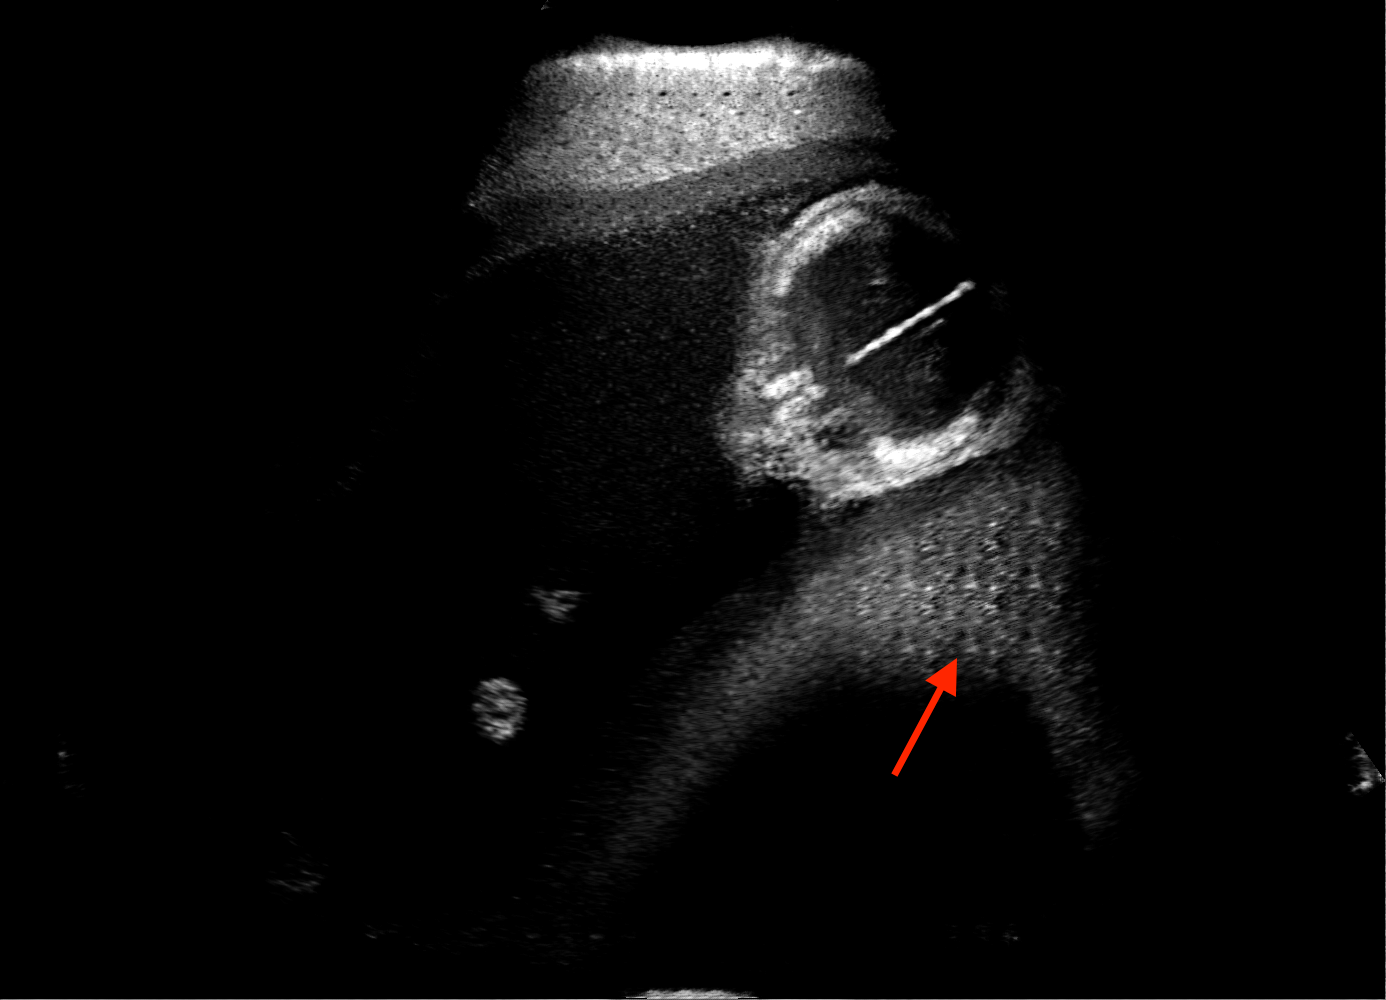

For the interpretation of the local errors, sample spatial p error maps are depicted in Fig. 3 for LSA2H, NSA2H, and SA2H for the middle two examples shown in Fig. 2. Both images generated by NSA2H have a lot of missing structures and accordingly have high error almost all over the map. Artificial skull enhancement with LSA2H is seem to evoke large p error, as shown in the corresponding error map, whereas the bright spots in the error map of SA2H reflect some hallucinated shadows and structure in the brain. All of above mentioned regions of interest are marked by red arrows. In the bottom example, SA2H fails to generate faithful content at the bottom region marked by red circles, which is well indicated by the error map as well.